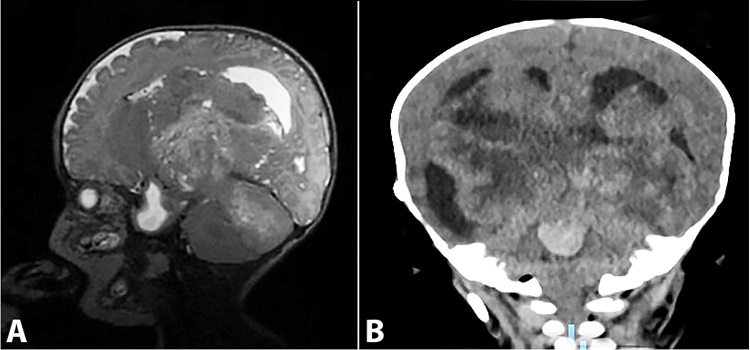

A female baby was born by uneventful vaginal delivery at 36.5 weeks' gestation with an APGAR score of 8 and 9 at the first and fifth minutes, respectively. Her weight was 2.3 kg, her length was 48 cm, and her cephalic perimeter was 28 cm. The mother was 39 years old (gravida 6: three cesarean sections, two vaginal deliveries, one abortion) who attended prenatal consultation during the first trimester of pregnancy. On the baby's first day, she had ocular secretion, jaundice, hyporeactivity, and slow suction reflexes. On day 3, she presented six apnea episodes. A transcranial ultrasound reported obstructive hydrocephalus. The MRI (Figure 1A) showed a heterogeneous and cystic mass on the posterior cranial fossa, which compressed ventricles III and IV, causing severe dilatation of the ventricular system.

The patient was submitted to an exchange blood transfusion on day 6, which resulted in clinical improvement. The neurosurgery team proceeded with a suboccipital craniotomy on day 21, resecting 40% of the total mass, which, on day 24, was complicated by a serous-draining fistula. One week later (day 31), the patient presented respiratory distress and oxygen desaturation due to Klebsiella pneumoniae pneumonia and required orotracheal intubation and an antibiotic regimen with vancomycin and levofloxacin. On day 33, she presented clinical improvement; however, 1 week later (day 40), the intracranial pressure increased again. Hyperchloremic metabolic acidosis ensued, and the fistula continued to drain serous-sanguineous fluid. The patient started with partial and focal seizures that manifested in the upper right limb and included sucking movements. Computed tomography of her brain was performed and revealed active bleeding and increased mass volume with medulla oblongata involvement (Figure 1B). Her clinical status worsened with desaturation, edema, hypothermia, and ultimately with mydriatic and areflexic pupils. Cardiopulmonary arrest and death were declared on day 112.